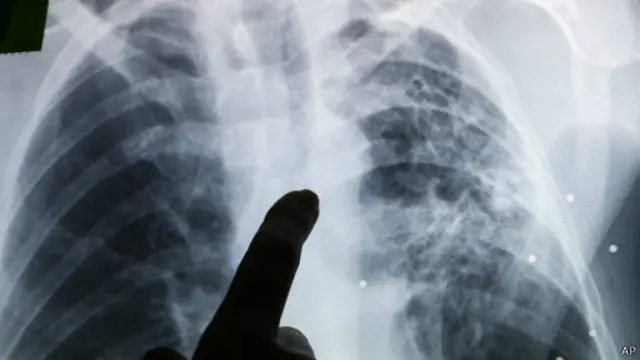

Tuberkulosis anak lebih tinggi dari prediksi

Lebih dari 650.000 anak di seluruh dunia terkena tuberkulosis setiap tahun, ungkap penelitian yang dipaparkan dalam jurnal Lancet Global Health.

Angka tersebut hampir 25% lebih tinggi dari prediksi saat ini yang dibuat oleh Organisasi Kesehatan Dunia.